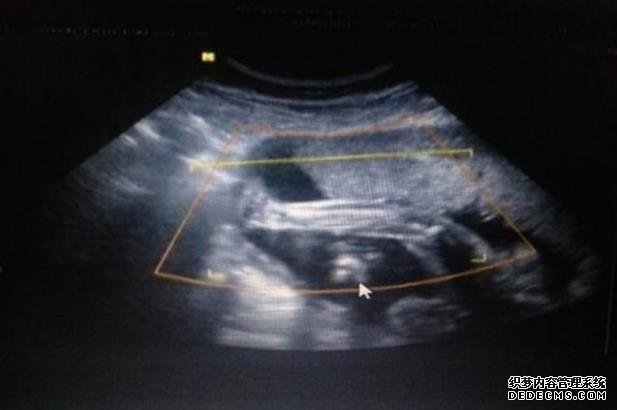

厦门求卵子 厦门医院试管是几代?厦门有可以做三代试管的医院吗? ‘孕囊9mm×6mm是男孩还是女孩’